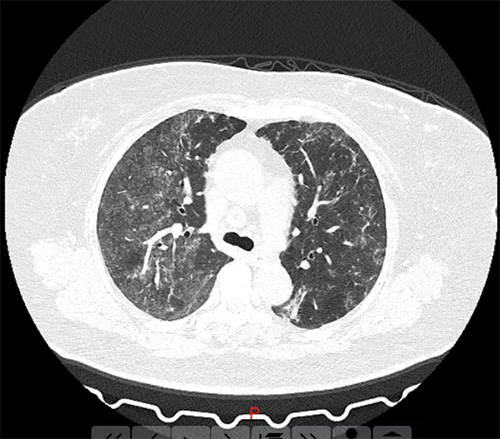

近日,河南郑州的张女士和王女士到医院就诊,结果胸部CT显示呈毛玻璃状,和新冠肺炎的CT表现基本一模一样。经询问,两人每天定时在家里喷洒高浓度的84消毒液,从而引起过敏性肺泡炎。主治医生李凤芝说:“张女士和王女士她们两个都是以头晕、乏力、闷气入院的,在疫情期间,常规查了胸部CT,结果显示呈毛玻璃状。”

王女士肺部CT

李凤芝还称,从CT影像来看非常像新冠肺炎,但是病人的接触史、症状表现,包括血象也是不符合的。

主治医生张小红主任称,张女士和王女士在家里使用84消毒液,确定是一个过敏性肺泡炎!

张小红还表示,通过询问两位女生对84消毒液的配比时,发现她们完全不知道,只是在电视上看到用84消毒液加点水一混,就在屋里消毒,消毒以后又没有开窗通风,长时间吸入了高浓度的84消毒液,就引起了肺部损伤。

接下来,医生把她们房间里的消杀用品换成酒精后,很快有了疗效。两三天以后复查片子,影像基本上都吸收完了。